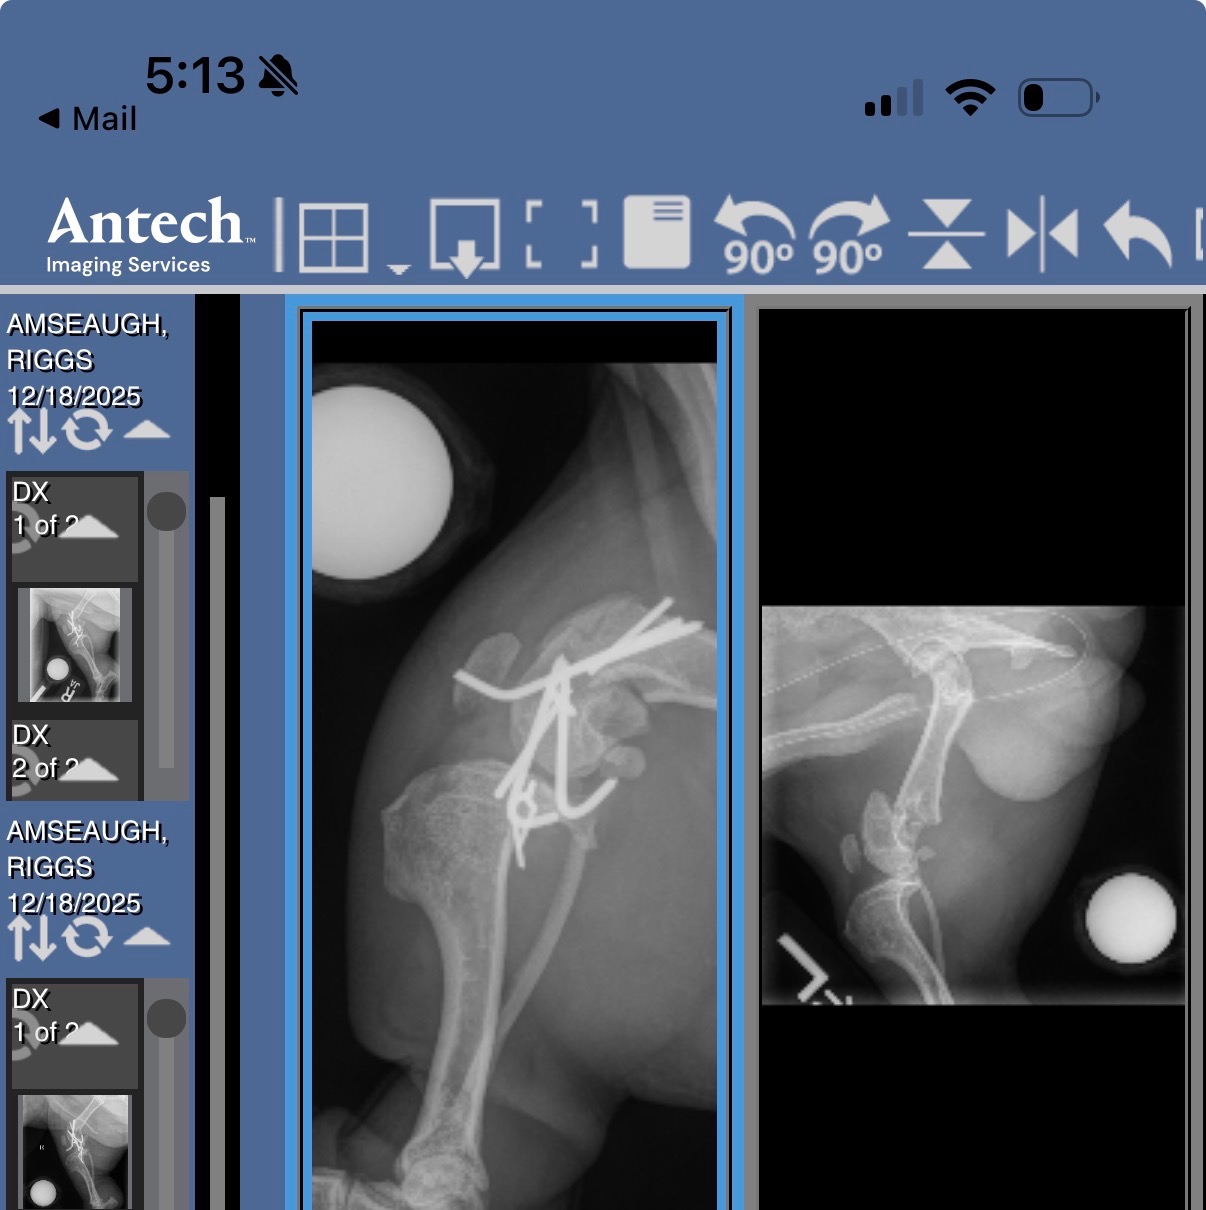

On Monday night, Riggs was hit by a car. The accident left him with two broken back legs and bruising in his ribs and lungs. Seeing him in pain has been heartbreaking, and I’m doing everything I can to make sure he gets the care he needs. The veterinarians have told me that Riggs will need orthopedic surgery to have any chance at a healthy, happy life. The procedure is complex and costly, but it’s his best hope for a full recovery.